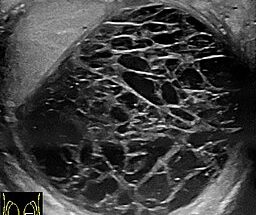

Czy siatka może się rozerwać?

ZERWANIE SIATKI PO OPERACJI PRZEPUKLINY PACHWINOWEJ? Siatka chirurgiczna jest stosowana w chirurgii przepukliny jako wsparcie dla mięśni i powięzi brzucha, aby aby nie powstał nawrót przepukliny. Siatka jest wkładana głęboko pod skórę pacjenta